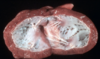

Q

ID + pathogenesis

A

Hypertrophic Cardiomyopathy – cats

- thickened LV walls (fails to relax) –> decr. diastole into LV (less volume capacity) –> incr. backflow into LA –> 2º LA dilation –> left-sided congestion